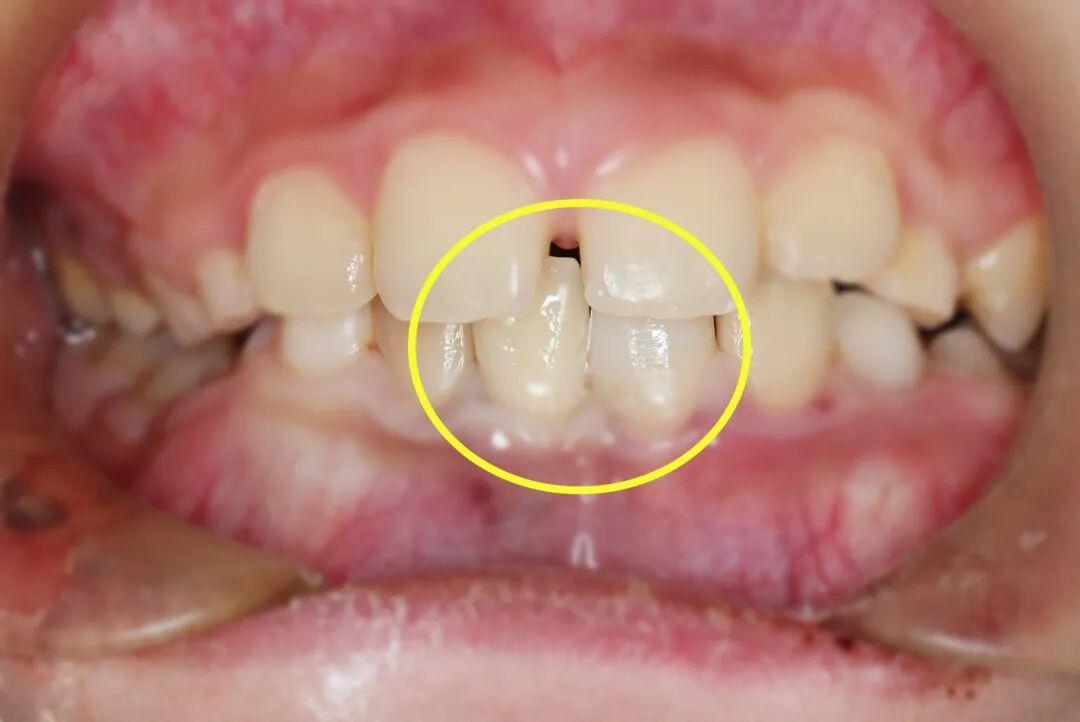

救治团队小心翼翼地接过家长带来的脱落牙齿,用专业工具轻柔清理牙根表面的污染物,确保不损伤牙根组织,随后精准将牙齿植入原来的牙槽窝,再用特制纤维带将其与相邻健康牙齿紧密结扎固定,为牙齿重新愈合提供稳定支撑,整个再植过程一气呵成。

针对冠折露髓的牙齿,救治团队在无痛辅助和显微镜下,彻底清除根管内的感染组织,进行严密的三维根管填充,建立无菌的内部环境。紧接着采用仿生树脂材料,通过分层分色堆塑技术,精准复原牙齿的天然形态和色泽,既解决了感染隐患,又恢复了牙齿的美观和咬合功能。